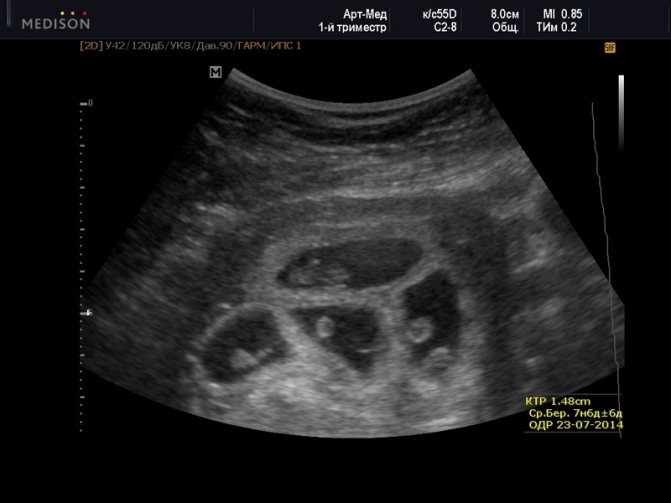

Какие параметры исследуются на ранних сроках, что видно на фото УЗИ?

Как выглядит двойня на ранних сроках? Поначалу врач видит только два темных пятнышка. Кроме того, отчетливо прослушивается биение двух сердец, видны две плаценты и два амниотических пузыря. На фото можно увидеть снимок УЗИ близнецов.

На ранних сроках при проведении УЗИ оцениваются следующие параметры плода:

- копчико-теменной размер — КТР, близнецы обычно имеют меньшие размеры, чем одиночные эмбрионы, и к 12 неделе достигают роста 6 см и массы тела 8 г;

Нередко на снимке УЗИ заметно, что один эмбрион меньше другого. Если расхождение невелико и составляет всего лишь несколько миллиметров, то беспокоиться не нужно, размеры выровняются или в процессе беременности, или после рождения малышей.